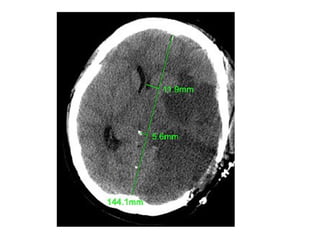

Midline Shift

b) Generalized Mass Effect :

-Ventricular or basal cistern effacement +/-

midline shift (subfalcine herniation) or other

herniation syndromes : uncal , transtentorial